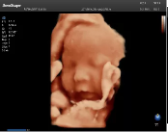

4容積探頭

積探頭是在二維圖像的基礎(chǔ)上,將連續(xù)采集的空間分布位置,經(jīng)過計(jì)算機(jī)重建算法,從而獲得完整的空間形態(tài)。

適用于:胎兒面部、脊柱和肢體等。

優(yōu)勢(shì)特點(diǎn):快速獲取、掃查連續(xù)均勻、解剖結(jié)構(gòu)顯示為容積數(shù)據(jù)、準(zhǔn)確進(jìn)行容積測(cè)量。